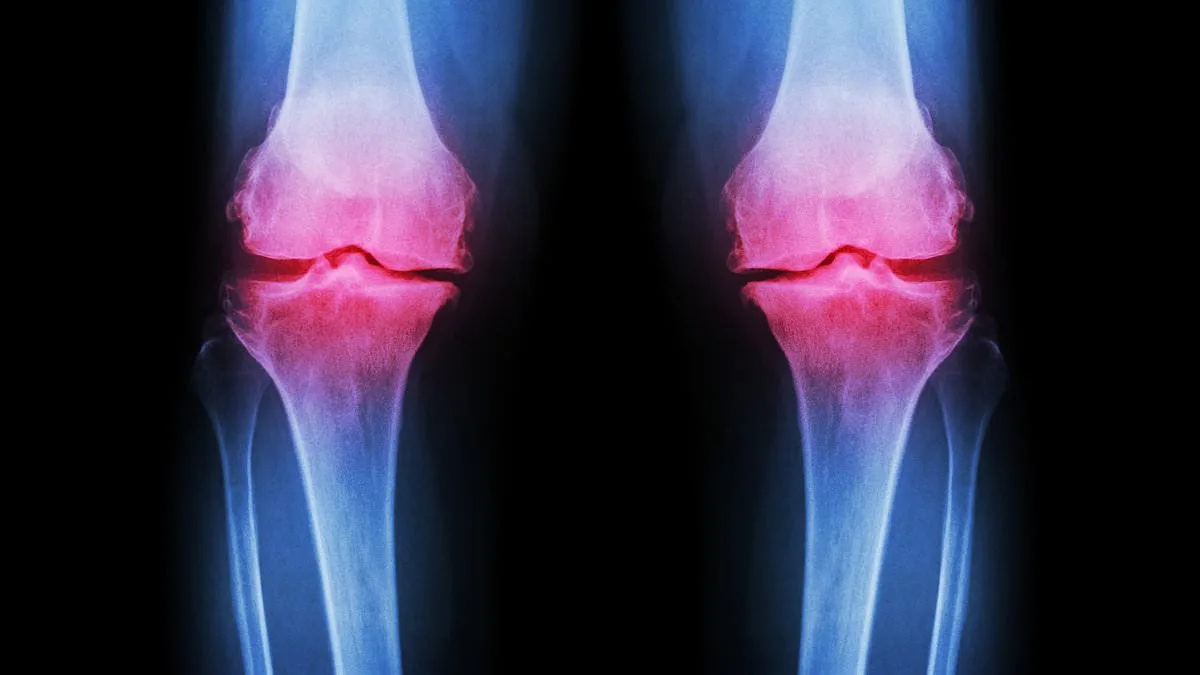

Osteoarthritis occurs when protective cartilage on joints wears down, leading to pain, stiffness, and reduced mobility. While joint damage is a normal part of life, the body typically repairs it. However, excessive stress from high-impact exercise and poor nutrition can overwhelm this natural process. Factors such as genetics, obesity, repeated stress on joints, and injuries all contribute to cartilage degradation. Post-traumatic osteoarthritis, for example, can result from fractures that affect joints, altering their mechanics and accelerating cartilage breakdown.